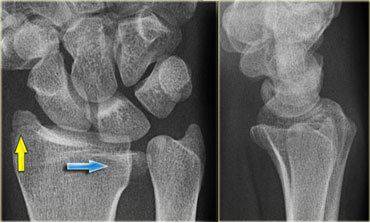

Galeazzi骨折

盖氏骨折:桡骨干骨折伴下尺桡关节脱位。